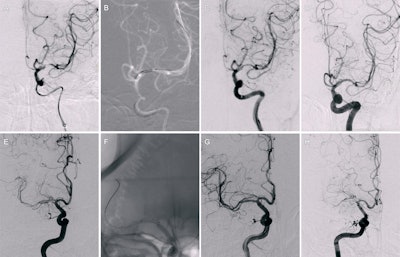

Example angiographic images from drug-coated balloon (DCB) angioplasty and bare-metal stent (BMS) placement procedures. (A-D) Images in a 49-year-old female participant who underwent DCB (2 × 9 mm) angioplasty for severe stenosis in the M1 segment of the left middle cerebral artery. Images (A) before and (B) during the procedure are shown. (C) Image immediately after the procedure shows improvement of the stenosis. (D) Image at 6-month follow-up examination reveals no restenosis. (E-H) Images in a 55-year-old male participant who underwent BMS (2.5 × 9 mm) placement for severe stenosis in the M1 segment of the right middle cerebral artery. Images (E) before and (F) during the procedure are shown. (G) Image immediately after the procedure demonstrates significant improvement of the stenosis, but (H) image at 6-month follow-up examination shows the development of restenosis and occlusion.Example angiographic images from drug-coated balloon (DCB) angioplasty and bare-metal stent (BMS) placement procedures. (A-D) Images in a 49-year-old female participant who underwent DCB (2 × 9 mm) angioplasty for severe stenosis in the M1 segment of the left middle cerebral artery. Images (A) before and (B) during the procedure are shown. (C) Image immediately after the procedure shows improvement of the stenosis. (D) Image at 6-month follow-up examination reveals no restenosis. (E-H) Images in a 55-year-old male participant who underwent BMS (2.5 × 9 mm) placement for severe stenosis in the M1 segment of the right middle cerebral artery. Images (E) before and (F) during the procedure are shown. (G) Image immediately after the procedure demonstrates significant improvement of the stenosis, but (H) image at 6-month follow-up examination shows the development of restenosis and occlusion.RSNAAccording to the results, the six-month angiographic restenosis rate was lower in the DCB group than in the BMS group (11% vs. 29%; p = 0.006). The DCB group also had a lower six-month symptomatic restenosis rate (1% vs. 10%; p = 0.02) and lower 30-day to one-year recurrent ischemic event rate (4% vs. 13%; p = 0.04). The 30-day stroke or death rate was similar between the groups, the researchers reported.